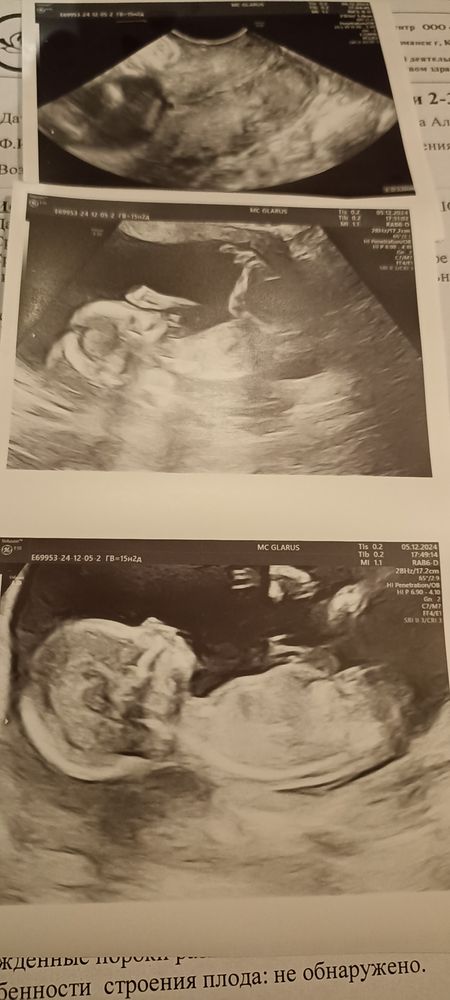

15 недель 2 дня

Вчера ездили на узи вместе с мужем.

Изображение

С малышом все хорошо, брыкается, сосет пальчик. По размерам опережаем на 1 неделю. Рост не сказали, а вес 145 гр. Еще